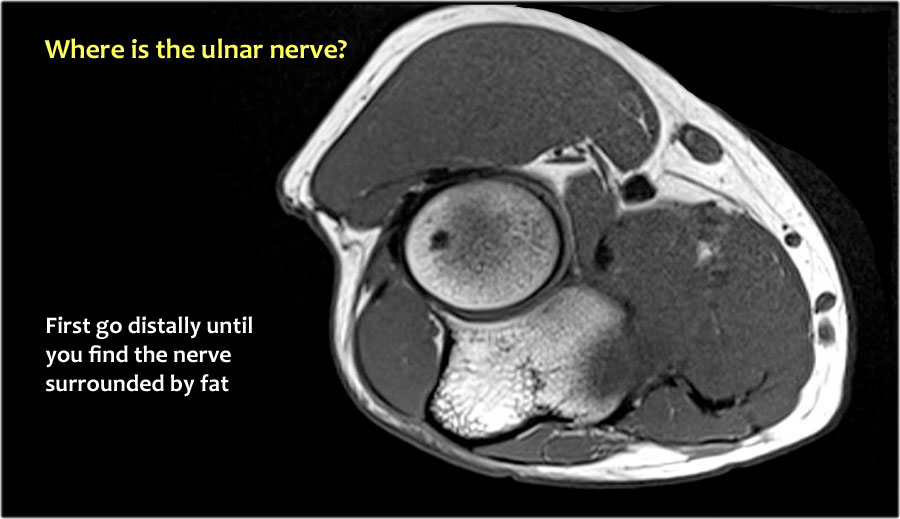

Vì vậy, khi chúng ta quay lại hình ảnh, bạn sẽ nhận thấy rằng có thể khó tìm thấy dây thần kinh.

Bất kỳ cấu trúc dưới da nào trong số này đều có thể là dây thần kinh đã được chuyển vị.

Một cách để thực hiện là đi theo các cấu trúc về phía xa cho đến khi tìm thấy dây thần kinh trụ ở phía xa tại vị trí bình thường của nó ở vùng cẳng tay gần được bao quanh bởi mô mỡ.

Sau đó khi bạn theo dõi nó về phía gần, bạn sẽ nhận thấy rằng đây là một trường hợp chuyển vị dưới da.